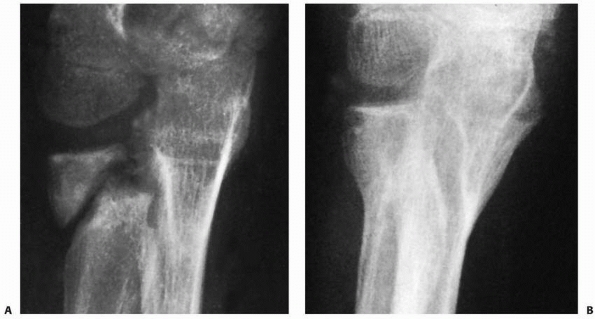

![]() |

FIGURE 11-23 Wallace radial head reduction technique. A. A periosteal elevator is used to lever the distal fragment laterally while the thumb pushes the proximal fragment medially. B. Kirschner-wires are used to assist the reduction if necessary. C. The position of the reduction can be fixed with an oblique Kirschner-wire.

|

FIGURE 11-24 A. Radial neck fracture angulated 45 degrees in a 14-year-old female. B. Radiograph after closed reduction using thumb pressure on the radial head. C. Final reduction after manipulation of the distal fragment with an elevator using the Wallace technique. D. Lateral view of the elbow after reduction.